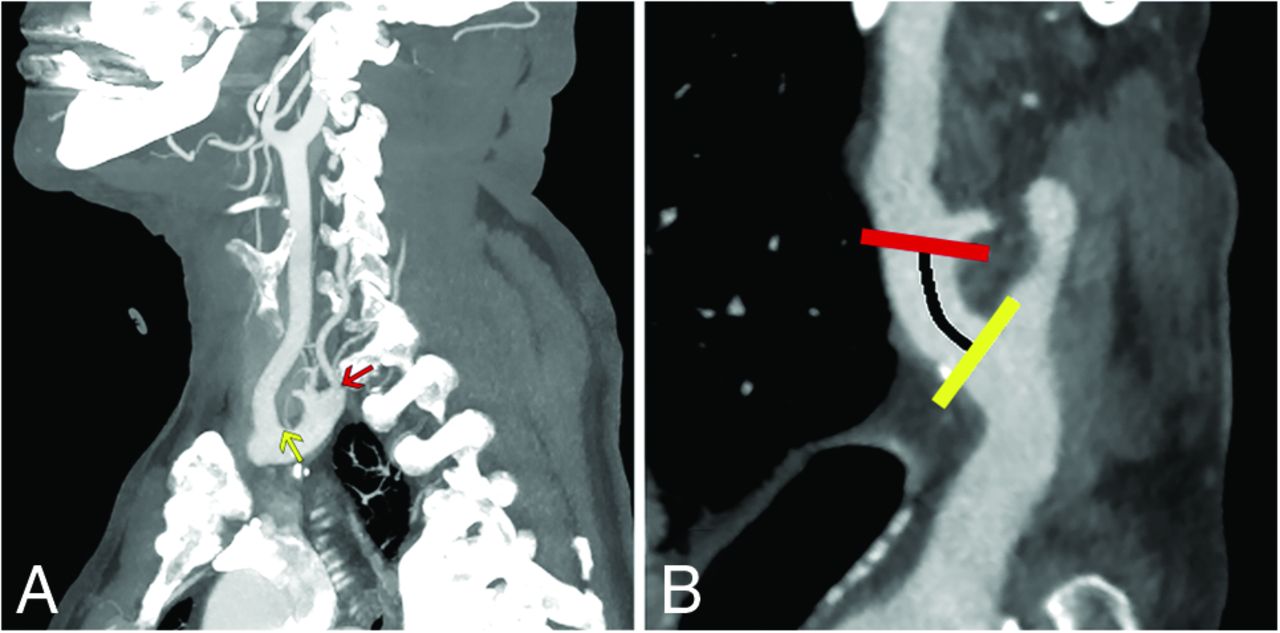

Quantification of the distance from the right SCA origin to the origin of the RVA. A, Sagittal MIPs show the origins of the RSCA (yellow arrow), defined as the distal wall of the origin of the right common carotid artery and the RVA (red arrow). B, Curved planar reformat shows a straightened SCA with estimation of the distance to the RVA origin along the SCA (black line indicates distance; yellow line, RSCA origin; red line, RVA origin).

CTAs of the neck were obtained for a variety of indications, including stroke, trauma, nontraumatic hemorrhage, vertigo, abnormal findings on carotid Doppler ultrasound, and follow-up for findings noted on earlier studies. CTA was performed according to institutional procedures, by using either a 64- or 128-section scanner (LightSpeed VCT or Revolution GSI, respectively; GE Healthcare) with bolus tracking following administration of Omnipaque 350 (GE Healthcare) into the venous system at a rate of 4 mL/s. Slices (0.625-mm-thick) were obtained from below the aortic arch through the circle of Willis or through the entire head, depending on the indication. Coronal and sagittal reformats were obtained, and MIPs were generated. 3D volume-rendered reformats were generated using dedicated software (Syngo Via; Siemens) (Fig 1). The same software was used to generate the images in subsequent images. Measurements of distances along the parent arteries to the origins of the VAs were obtained by generating curved planar reformats and measuring linear distances along the parent vessels (Fig 2). Cases with VA variants were identified and compiled in a deidentified file on a Health Insurance Portability and Accountability Act–compliant encrypted server. This study was exempted from institutional review board review by the Rutgers University Institutional Review Board (Pro 2022000874).

Box-and-whisker plot showing the distance from the origin of the RSCA for right VAs entering the FT from C3 through C7. Although there is some overlap, high-entry VAs originate more proximally than arteries entering at C6. There is more heterogeneity in low-entry VAs, which may originate from the aortic arch (negative numbers on this figure) or along the RSCA. For this figure, all low-entry VAs are considered together, without regard for whether they share a common origin with the CCT.

Variants in right VA anatomy are illustrated in Fig 3. The most common variant encountered on the right was the artery originating within 2 cm of the right common carotid artery (30 cases, Fig 3C), with entry to the FT at C5. This was the only variant that demonstrated a statistically significant sex predilection, occurring more commonly in men than in women (21 versus 8, respectively, P = .016). Entry at C3 or C4 was also associated with proximal origin on the RSCA (Fig 3A, -B and Fig 4), and these vessels frequently originated even more proximally than those entering at C5. Entry at C7 was associated with origin either at the distal aortic arch or along the more distal RSCA (Fig 3D).

When the distances of the VA origins on the right were grouped by their FT entry level, there was some overlap, particularly between origins of vessels entering at C5 and C6 (Fig 4). However, there was good overall separation between these groups, and nearly no overlap between “typical” origins and those entering the FT at C3 or C4, which originated more proximally on the RSCA. The origin of arteries entering at C7 from the aortic arch (negative numbers in Fig 4) as well as at more distal locations along the RSCA contributed to a wide range of values for this subset of arteries.